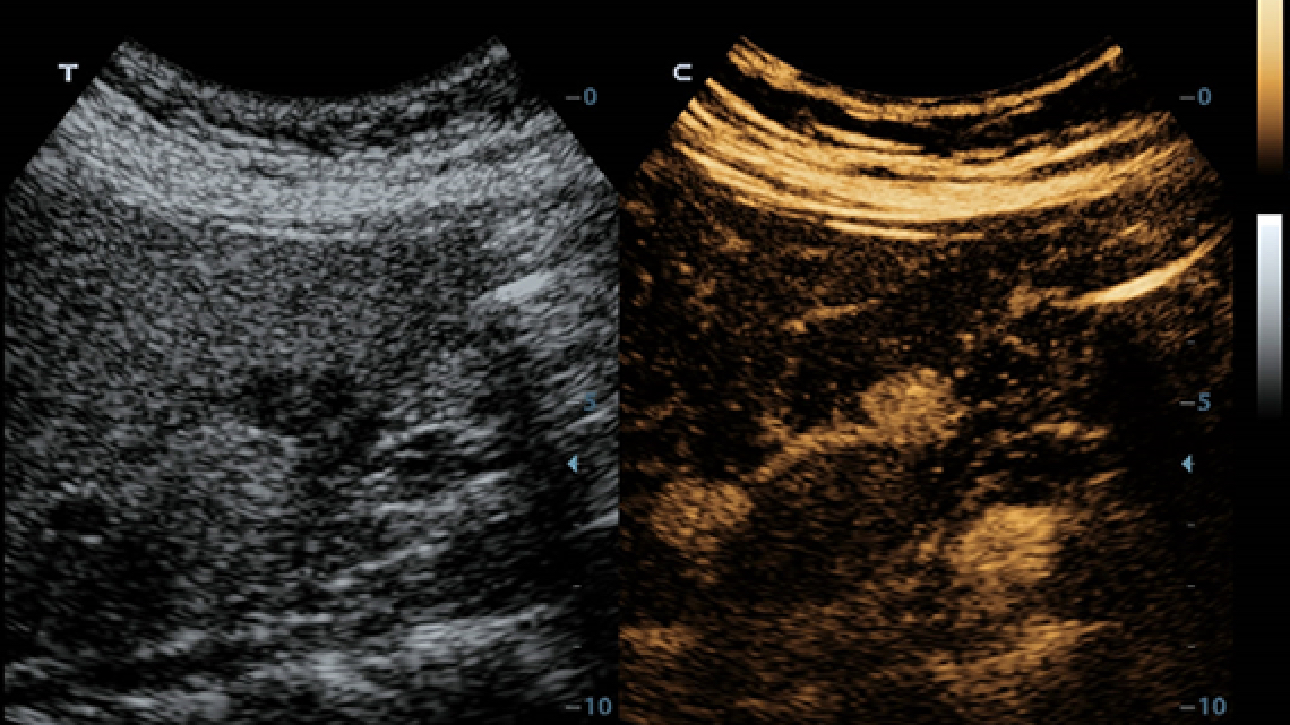

MĂŒ?teri gereksinimlerine y?nelik g?rĂŒ?ler temelinde, X-Insight'l? DC-60 Exp, eXpress Clarity, eXceptional Intelligence ve eXceeding Experience ile gĂŒ?lendirilerek, hassas g?rĂŒntĂŒlemeyle yĂŒksek verimlilik sa?layacak ?ekilde tasarlanm??t?r.

eXceeding Experience

YĂŒksek verimli deneyim